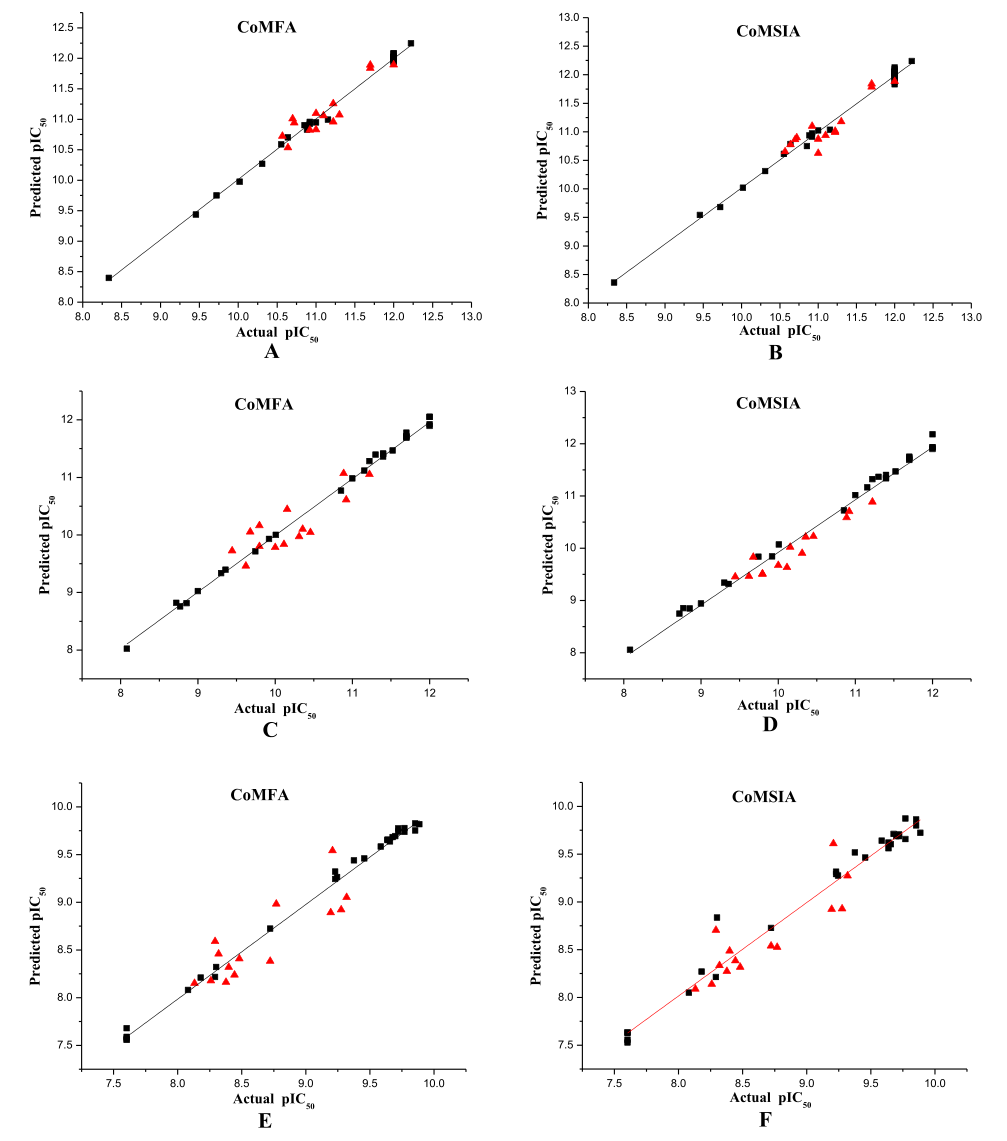

4.3.8 QSAR

4.3.8 QSAR

QSAR,全称为定量结构-活性关系(Quantitative Structure-Activity Relationship),是一种在计算化学和分子模拟中广泛使用的方法。它通过研究化合物的结构特征与其生物活性之间的数学关系,来预测新化合物的活性。

在分子动力学模拟中,QSAR可以应用于模拟和预测化合物的行为。例如,通过研究已知药物分子的结构和活性,可以构建一个QSAR模型,然后使用这个模型来预测新的化合物是否可能具有类似的药效。

QSAR模型通常包括一系列描述化合物结构的参数(称为描述符),这些描述符可能包括化合物的大小、形状、电子性质、极性等。通过统计分析,可以找出这些描述符与化合物的生物活性之间的关系,从而构建QSAR模型。

然而,QSAR模型的准确性和可靠性取决于许多因素,包括用于构建模型的数据集的质量和大小,描述符的选择,以及用于建模的统计方法等。因此,虽然QSAR是一个强大的工具,但在使用时需要谨慎。